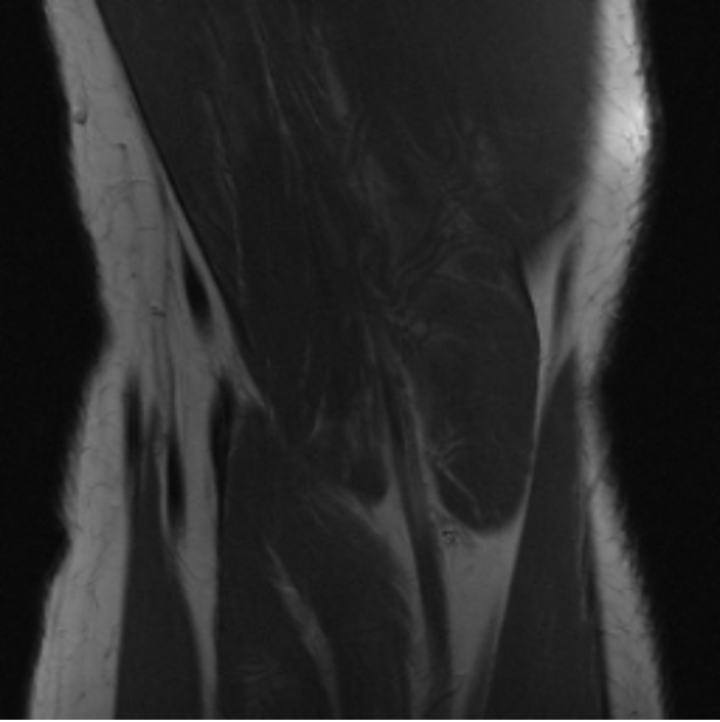

5.3 Out-of-Domain Generalisation

One way to test the generalization capability of the trained X-Diffusion is to test it on a completely different domain from an MRI dataset not seen during training. We report the single-slice results on NYU fastMRI [37, 82], a knee MRI dataset, using the X-Diffusion trained on the BRATS brain MRIs. The results are shown in Figure 9 and Table 2. It shows how successfully X-Diffusion is able to generate knee MRIs from a single image, despite not seeing knees at all in training. To qualitatively assess how realistic our generated 3D volumes were (produced from a single slice), we gave 20 generated examples alongside their real MRI counterparts to an expert orthopaedic surgeon. He was then asked to identify the real example from a given pair. The surgeon identified with certainty only 10 real knee MRIs out of 17, while could not decide on the remaining 3 of the 20 MRI pairs. This further validates the generated out-of-domain MRIs.